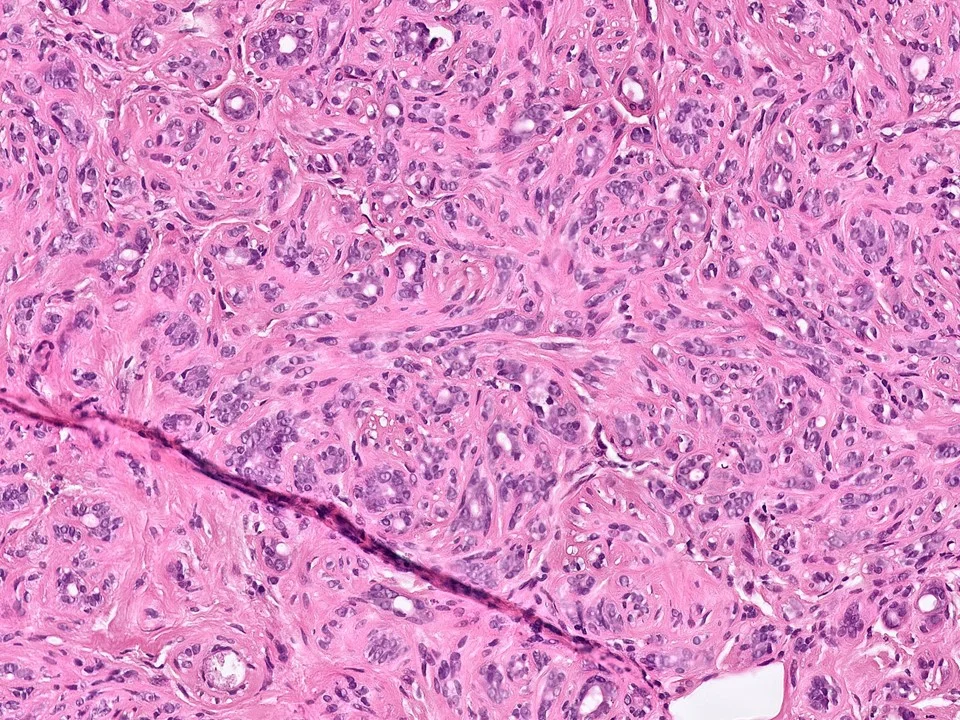

Invasive Ductal Carcinoma, Grade 3, With Extensive Lymphovascular Invasion

Invasive ductal carcinomas are the most common type of invasive breast cancer (70-75% of cases). They are heterogeneous with regards to pathologic features and clinical course.

Histologically, IDCs vary with regard to growth pattern (eg tubular vs solid), cytologic features, mitotic activity, stromal desmoplasia, and extent of associated in-situ component. The degree of gland formation, nuclear atypia, and mitotic activity are considered together in determining the combined histologic grade.

Three universally accepted biomarkers are used in daily practice currently: estrogen receptor (ER), progesterone receptor (PR), and HER2. Studies have shown about 70-80% of IDCs are ER+ and 15% show HER3 overexpression.